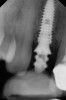

Fig 10. Periapical radiograph showing implant placement with abutment in place for fabrication of provisional crown.

Figure 10

When placing an implant in the esthetic zone, ideal 3-dimensional positioning, including mesio-distal, apico-coronal, and orofacial dimensions, is essential to achieve favorable esthetic outcomes, regardless of the implant system used (Figure 6).45 With respect to the orofacial dimension, implants should be placed in a more palatal or lingual position to allow the presence of at least 2 mm of buccal bone thickness from the implant buccal shoulder.45,46 When the distance of the buccal bone wall and implant buccal shoulder is < 2 mm, a significantly higher incidence of midfacial recession has been previously reported.3,12 Placement of bone graft (Figure 7) and immediate restoration (Figure 8 and Figure 9) at the time of implant placement has also been suggested to increase peri-implant soft-tissue height and thickness.51 In the apico-coronal dimension, the implant head should be at least 3 mm apical to an imaginary line connecting the CEJ of the adjacent teeth and 1 mm to 2 mm apical to the interproximal and crestal bone to ensure a proper implant emergence profile and facilitate proper implant restoration (Figure 10). Regarding the horizontal implant–tooth distance, implants should be placed no closer than 1.5 mm from the adjacent root surface to minimize resorption of the interproximal alveolar crest, which causes a reduction in the papillary height.46,52